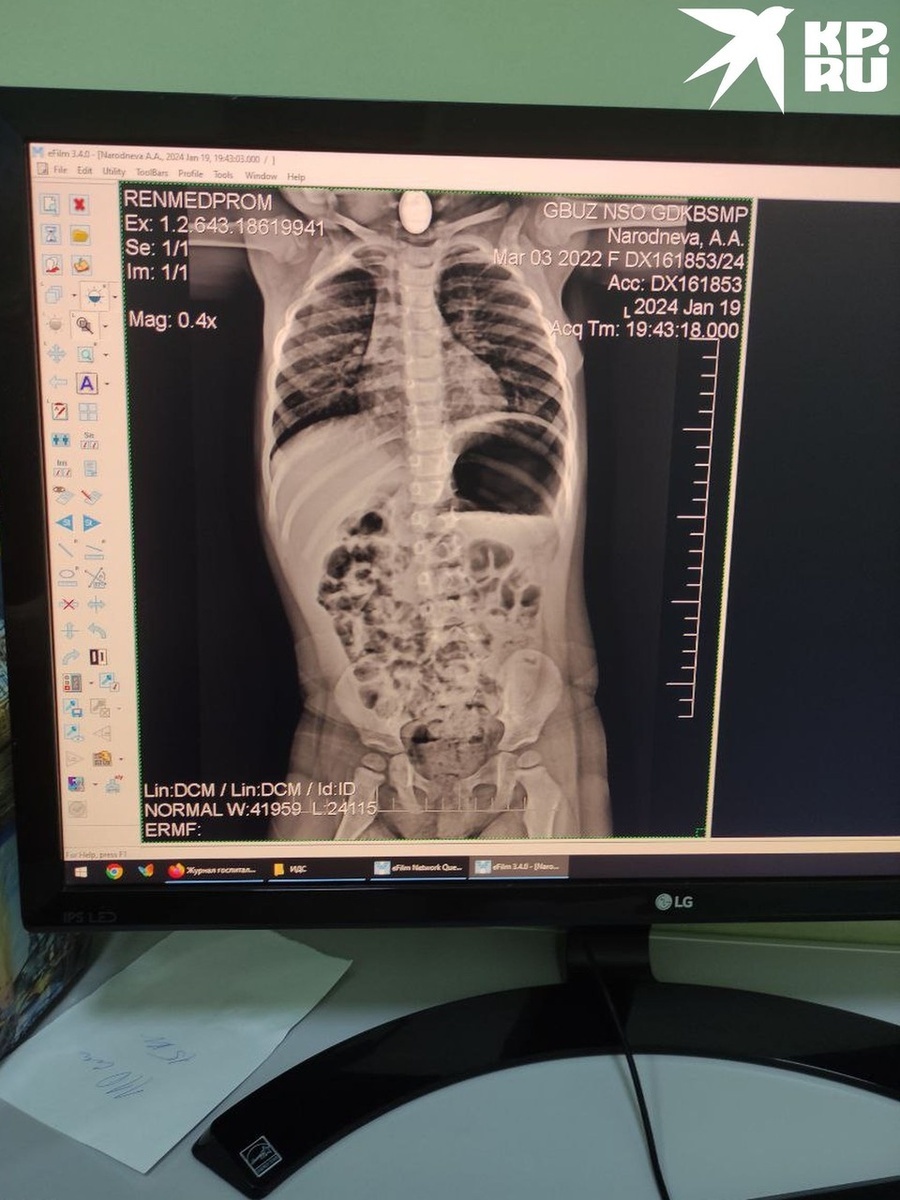

Семью отвезли в больницу, где сделали рентген и увидели застрявший предмет. Сибирячка вспоминает, что в этот же момент в больницу приехали родители с мальчиком примерно такого же возраста, который проглотил рубль.